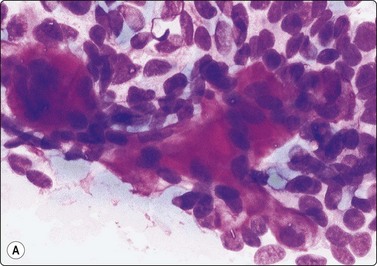

Fig. 4.6 Squamous cell carcinoma

Mainly poorly differentiated malignant cells with large vesicular nuclei and large nucleoli; a few squamous and keratinized cells. FNB smears of cervical lymph node metastasis from squamous carcinoma of larynx (A, MGG; B, Pap, HP).

Squamous cell carcinoma (SCC) is by far the commonest type of carcinoma encountered in the head and neck. Diagnostic criteria are listed in Chapter 8. Lymph node metastases of well-differentiated squamous carcinoma, particularly those arising in the Waldeyer’s ring, have a tendency to undergo liquefactive degeneration (see Fig. 4.3).41 The existence of primary SCC arising in a pre-existing branchial cyst has been doubted and is, in any case, an extremely rare event.42 The distinction from non-neoplastic cysts, mainly branchial cysts has been discussed above. Non-keratinizing squamous cell carcinoma may be represented in smears mainly by small basaloid cells in which case the differential diagnosis includes basal cell carcinoma, pilomatrixoma, poorly differentiated adenoid cystic carcinoma and other small cell tumors. Cells from a poorly differentiated squamous cell carcinoma have large vesicular nuclei and macronucleoli and resemble other anaplastic tumors such as melanoma and large cell lymphoma (Fig. 4.6).